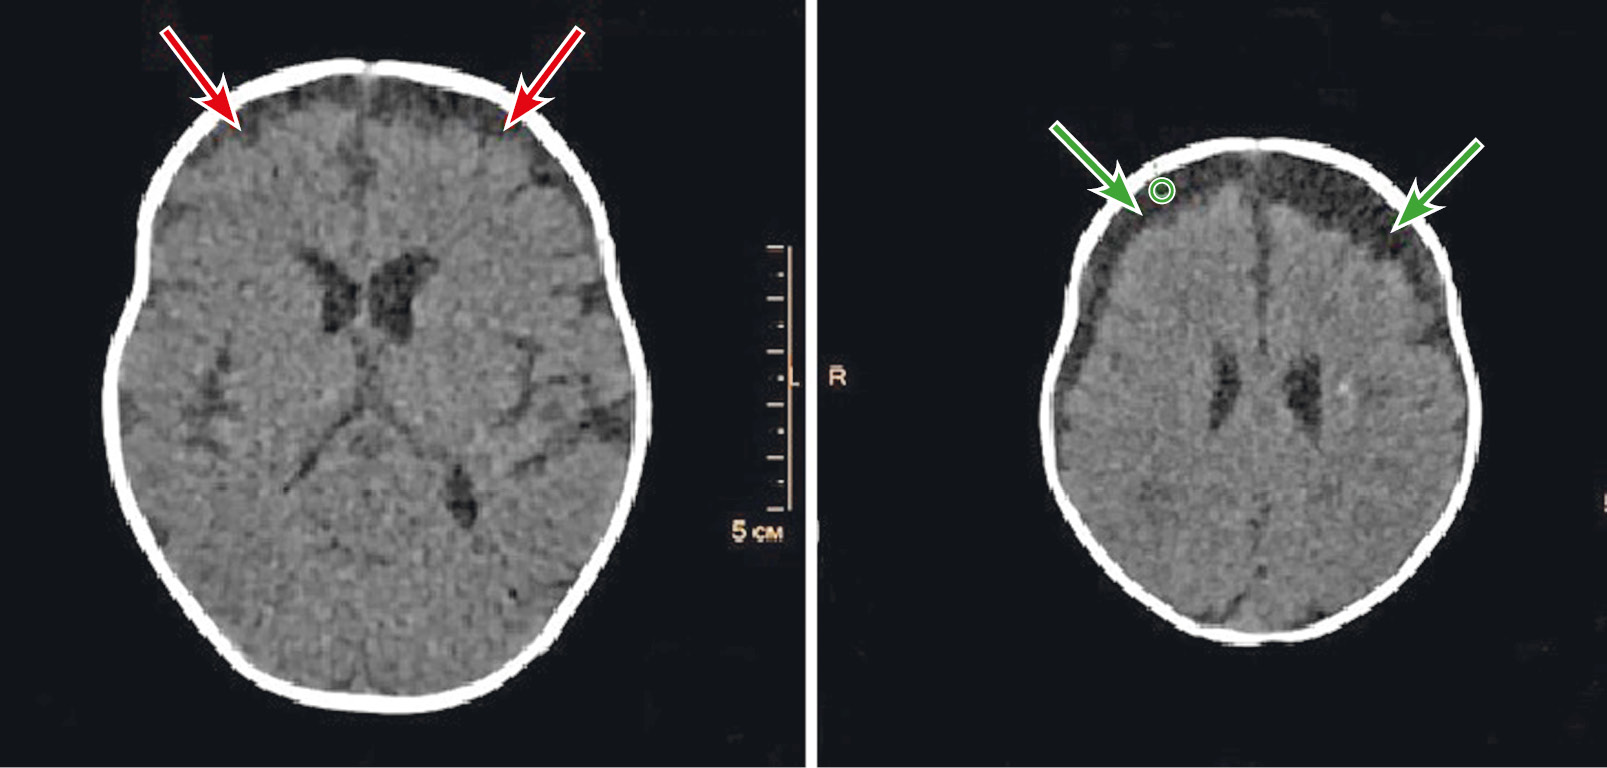

Необходимо дифференцировать субдуральный выпот от субдуральной эмпиемы, т.к. последняя может вызвать такие осложнения, как тромбофлебит и энцефалит. При эмпиеме плотность жидкости немного выше на КТ-изображениях (рис. 5), имеет повышенный МР-сигнал на Т1-ВИ и FLAIR-изображениях из-за более высокой концентрации белка. При внутривенном контрастировании оболочки эмпиемы умеренно накапливают контрастное вещество. С появлением DWI дифференцировка простого выпота и эмпиемы при МРТ стала более доступной: эмпиема показывает более высокий сигнал на DWI>800 c/мм2 и низкие значения ADC, такие же как в абсцессе. Протонная МРС может дополнять DWI и обычное МР-изображение. Некротическая жидкость бактериального абсцесса в поздней стадии лишена нормальных метаболитов головного мозга, таких как N-ацетиласпартат, холин и креатин.

Рис. 5. КТ (аксиальная плоскость) головного мозга пациента М., 4 мес, с диагностированным при поступлении менингитом неясной этиологии. Исследование выполнено в первые часы после поступления. Определяется расширение наружных ликворных пространств лобных областей с частично отграниченным скоплением белковой жидкости и формированием уровней седиментации (эмпиема указана стрелками). Фрагментарное неравномерное накопление контрастного вещества в паутинной оболочке: a — нативное сканирование; b — венозная фаза контрастирования (собственные данные).

Fig. 5. CT scan of the brain of a patient M., 4 months. Diagnosis at admission – meningitis of unknown etiology. The study was performed in the first hours after admission. The expansion of the external cerebrospinal fluid spaces of the frontal areas with a partially delimited accumulation of protein fluid and formation of sedimentation levels (empyema is marked by an arrow) is determined. Fragmented uneven accumulation of the contrast medium in the arachnoid membrane: a — CT scan of the brain, axial plane, native scan; b — CT scan of the brain, venous phase of contrast, axial plane (own data).